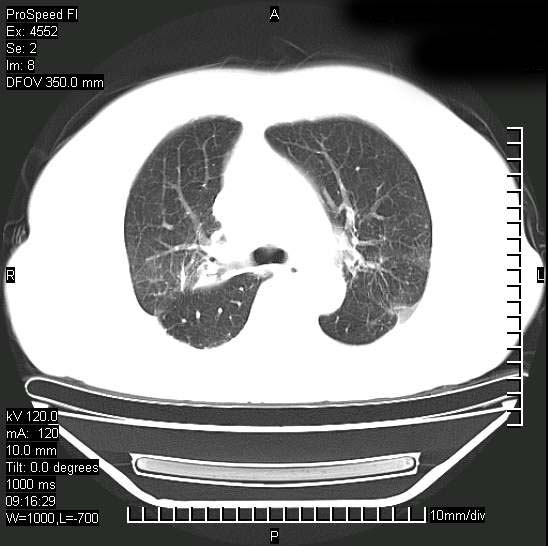

十几年前曾患肺结核,一周前突咳血约100ml,中性粒细胞稍高,诊断两上肺陈旧结核,下肺炎症,给予抗炎治疗,近几日晚上高热,39度,仍咳少量血,4天前ct及今天ct上传。

今天ct

短短几天内,病变范围明显增多扩大,以左侧明显,而且双侧出现胸水,还是考虑感染.

短短几天内,病变范围明显增多扩大,以左侧明显,而且双侧出现胸水,我更多考虑左侧中心性肺癌并并阻塞性不张及肺炎,炎症变化也太快了!

无论是肿瘤还是炎症4天的时间都发展够快的,并且还在治疗中,如果说是左肺癌那么右肺的病变不好解释,本人更加倾向于炎症,左肺舌叶支气管被痰栓或血凝块堵塞,造成阻塞性肺炎。

1)两肺结核并感染。2)不排除左肺上叶中央型肺癌并阻塞性肺炎、肺不张可能;建议行纤支镜检查。3)右肺门及纵隔淋巴结肿大。4)双侧胸腔积液。

陈旧性肺结核及左下肺不张,咯血后肺部感染,双胸腔积液,高热可能与痰液引流不畅有关。